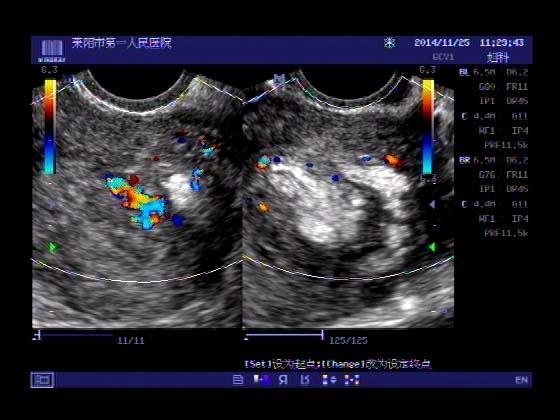

超声入门贴379---------粘膜下肌瘤(阴超的魅力)

女,43岁,月经量多3个多月,加重一个月

外院彩超检查提示:子宫后肌壁略高回声团------肌瘤?息肉?,盆腔少量积液

今天来我院检查:

巧妇难为无米之炊,经腹部超声确实很难定,阴超一目了然,乡镇医院诊断水平的提高更迫切的需要高档仪器的引进!